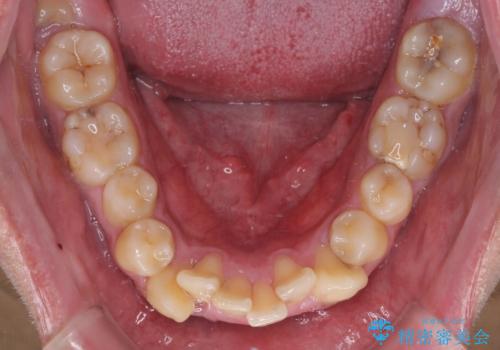

- 八重歯を気にして来院された患者様です。

上下左右の犬歯が八重歯になっており、口元にもやや突出感があるため、上下左右の小臼歯4本を抜歯し、ワイヤー装置にて矯正治療を行うこととしました。

患者様には辛抱強く治療にお付き合いいただき、すっきりとした口元に仕上げることができました。